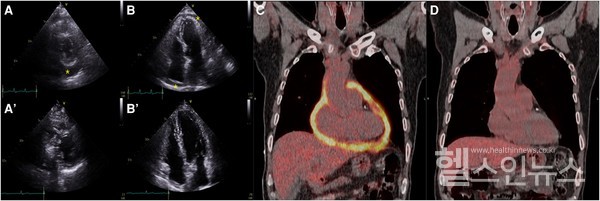

가톨릭대학교 서울성모병원 심뇌혈관병원 순환기내과 정미향(교신저자), 핵의학과 오주현(공동 제1저자) 교수 연구팀은 최근 심장초음파와 양전자단층촬영(18F-FDG PET/CT)의 다학제 영상 검사를 결핵성 심낭염의 초기 진단뿐 아니라 치료 경과 확인에 이르기까지 활용하여 효과적으로 치료하였다.

이제까지 결핵성 심낭염의 감별 진단으로 심장초음파, CT, MRI, 양전자단층촬영을 비롯한 각종 영상 검사와 검체 검사를 병행하는 복합적인 전략이 제시되어 왔지만, 치료 후 경과 평가 방법은 아직 구체적으로 정립되어 있지 않았다. 그러나 연구팀은 심장초음파 검사에 양전자단층촬영을 보조적으로 활용하면, 환자의 심낭 내 염증 개선 정도를 정량적으로 확인할 수 있어 치료 평가에 유용하다고 설명했다.

결핵성 심낭염은 일반적으로 6개월간 항결핵제를 복용 후 치료를 종료하게 되나, 염증의 충분한 개선 여부를 심장초음파만으로는 정확히 알기 어려운 한계가 있었다. 양전자단층촬영을 보조적으로 활용하여 치료 종료 시점의 염증 수준을 파악할 수 있다면 결핵성 심낭염의 재발이나 합병증으로 인한 유착성 심막염 위험을 최소화하는 한편, 개별화된 맞춤형 치료 전략을 수립할 수 있게 된다.